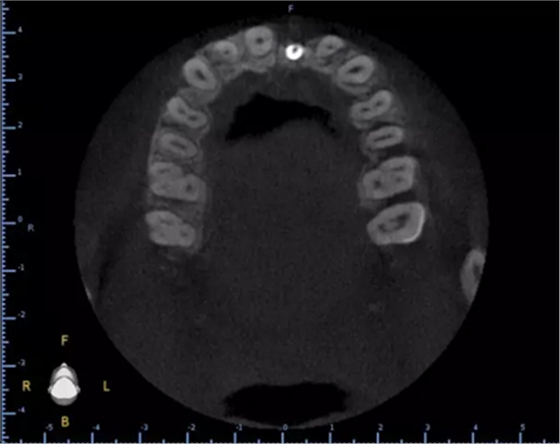

頜面部消毒→鋪襟→局麻下翻瓣→帶入導(dǎo)板→定位鉆定位→擴(kuò)孔鉆擴(kuò)孔→植入3.0x13植體→覆蓋螺絲→縫合→沖洗→術(shù)后醫(yī)囑

術(shù)后CT